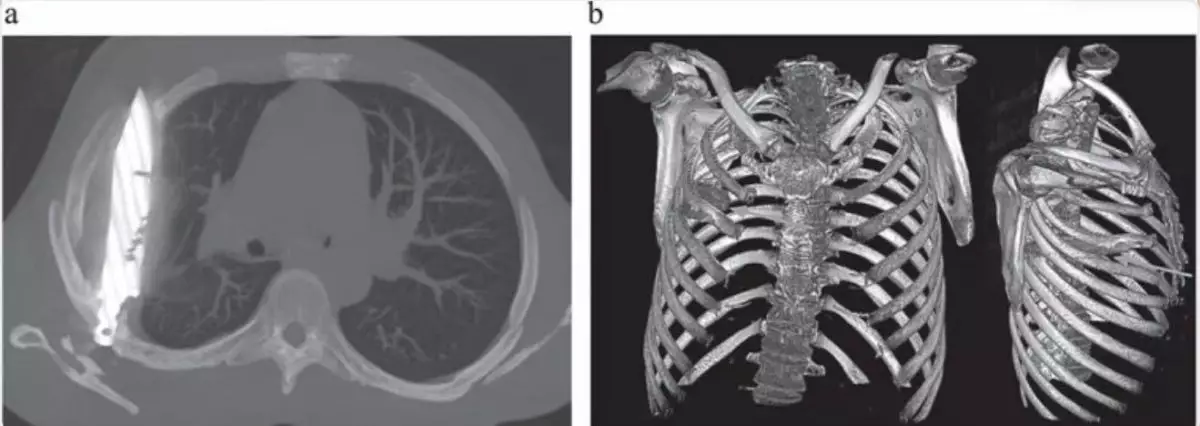

醫生隨後為男子安排X光檢查,結果發現胸腔內竟藏有一件利刃狀金屬異物,自肩胛骨位置刺入,四周被膿液及壞死組織包圍,令醫療團隊大為震驚。在醫生追問下,患者回憶起 8 年前曾捲入一場激烈衝突,當時臉部、背部、胸部及腹部均遭多處刀傷。然而,由於當地醫療資源匱乏,他僅接受表層傷口縫合,並無進行深入檢查,之後多年也未曾出現異常症狀。

經專科安排,男子立即接受手術移除刀片,術後恢復情況理想,於 10 天後順利出院。醫療團隊表示,「患者身體成功將異物包覆在纖維囊內,限制了發炎和組織損傷」,但乳頭開始流膿已是嚴重併發症前兆。他們強調,這枚殘留刀片原可造成致命風險,並呼籲提升資源不足地區的創傷處理能力及醫療設備,以免類似情況再度發生。目前,相關病例已刊載於《外科病例報告期刊》(JSCR)。